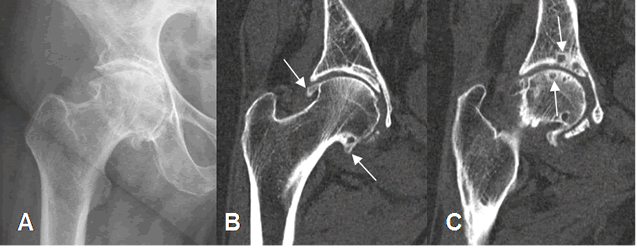

Fig 145. Artropatía degenerativa.

A: Rx AP. Cambios degenerativos con disminución asimétrica del espacio articular, esclerosis y formación de osteofitos. Alteración femoral por pinzamiento mixto.

B: y C: TAC reconstrucción coronal. Presencia de osteofitos en A y quistes subcondrales en B.